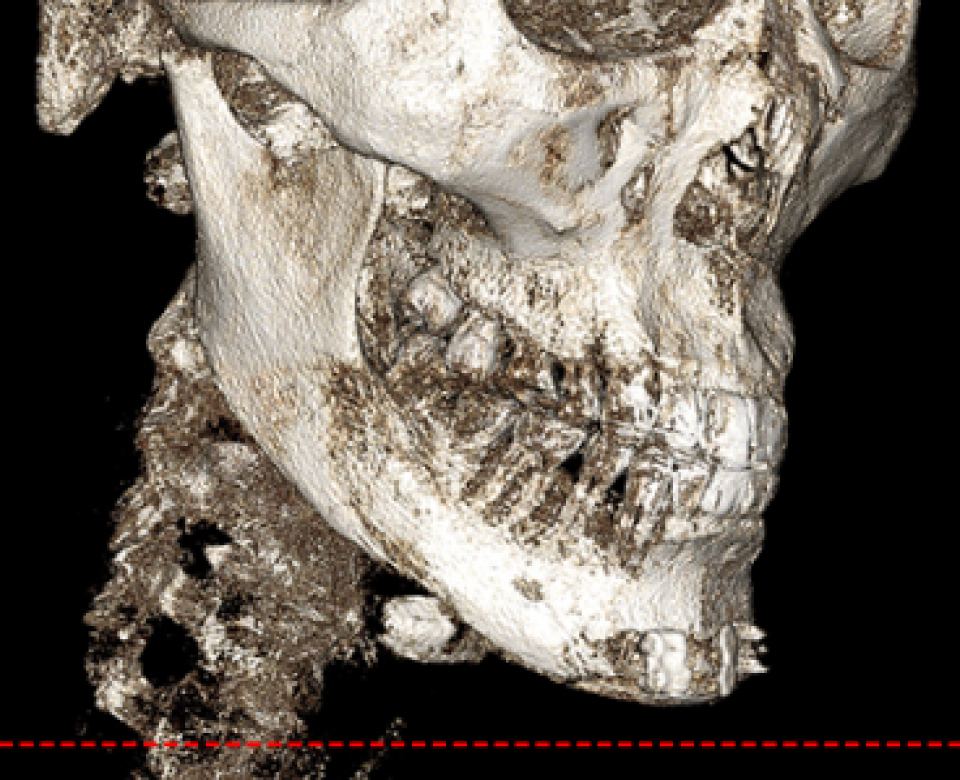

• 신경 보존 절골법 이미지

무분별한 절골은 감각 이상과 같은

심각한 후유증을 남길 수 있습니다

신경 손상을 최소화하여

안전을 최우선으로 합니다

수술 전 3D-CT를 통해 신경의 위치를

1mm까지 분석하고,

원장님이 직접 수술 경로를 디자인하여

신경 손상을 원천 차단합니다

* 수술전 원장님이 직접 디자인한 사진입니다